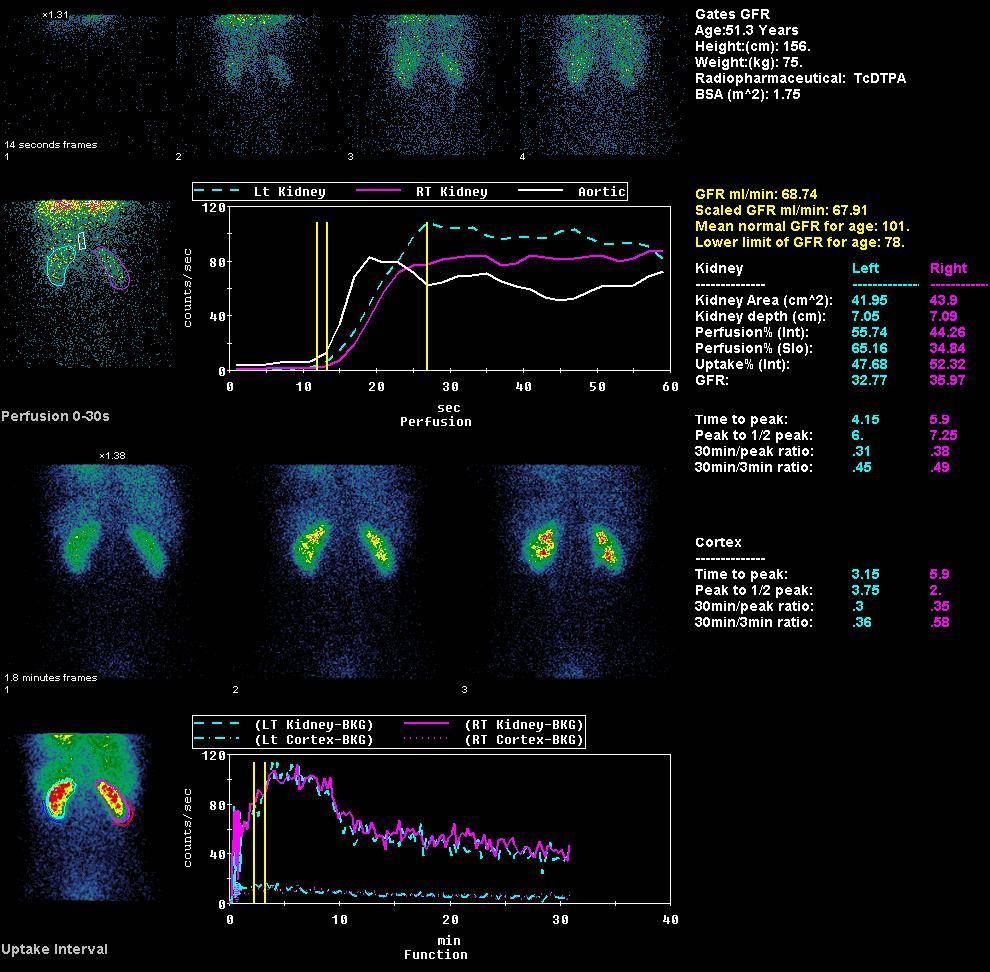

Динамическая нефросцинтиграфия: